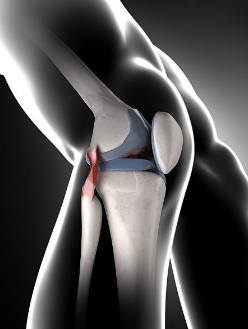

2. 내측 반월상 연골 손상

내측 반월상 연골은 무릎 관절의 쿠션 역할을 하며, 충격을 흡수하고 관절의 움직임을 돕습니다. 내측 반월상 연골이 찢어지거나 파열되면 무릎 안쪽 통증이 발생하며, 부기, 무릎의 잠김 현상, 관절의 움직임 제한 등의 증상이 동반될 수 있습니다. 내측 반월상 연골 손상은 스포츠 활동 중에 갑자기 방향을 바꾸거나 점프하는 경우에 자주 발생합니다.